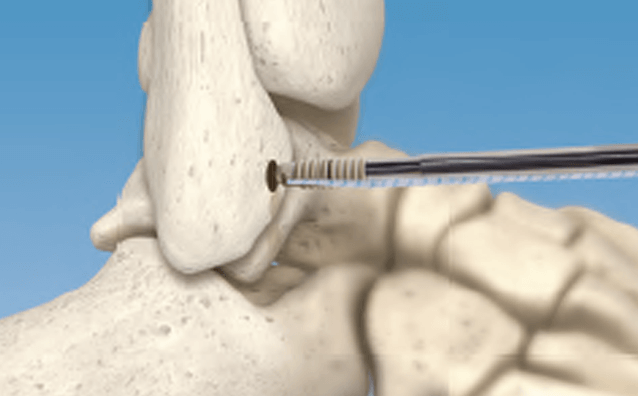

Dr. Gdalevitch - Minimally Invasive Percutaneous Approach for Hallux Valgus Deformities